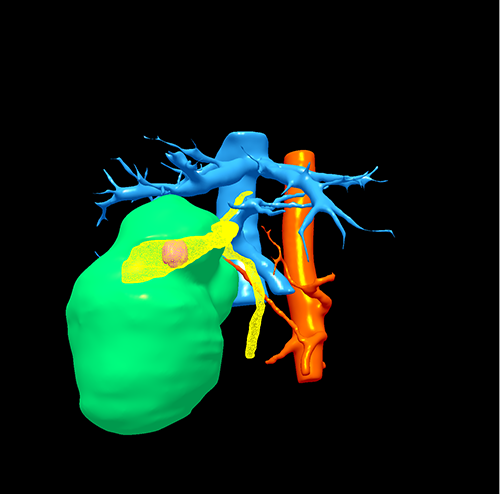

右肝胆管囊腺瘤----S5囊腺瘤切除、胆囊切除